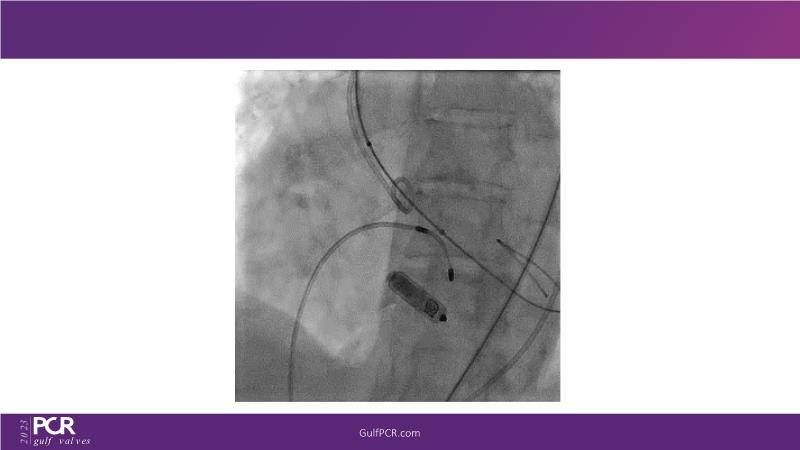

The primary focus of this GulfPCR-GIM 2023 session revolves around pre-procedural planning considerations, valve selection, and managing complex anatomies using both traditional self-expanding valves and the Evolut FX system. Additionally, the session aims to explore the work-up protocol for patients grappling with severe AS and advanced CKD, elucidate the algorithm for selecting the appropriate TAVR platform, discuss strategies to reduce contrast utilization, and highlight the distinctive advantages offered by the Evolut FX system.

• To learn more about optimization of valve deployment